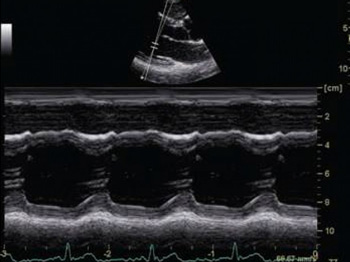

- B, M

Анатомический М-режим. Благодаря этой функции вы получите возможность сделать до трех срезов одновременно в реальном времени, вращая курсор под произвольным углом без перемещения датчика. Таким образом, врач может увидеть графику движения структур сердца